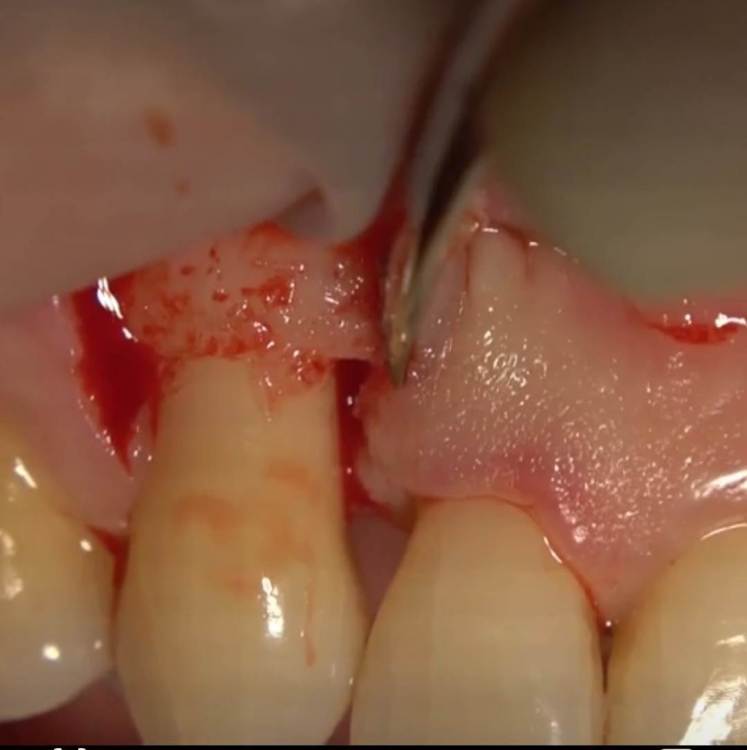

Aquarius Опубликовано 8 августа, 2023 Поделиться Опубликовано 8 августа, 2023 Будет правильным . Сосочек лучше не отрывать от кости. По Кортеллини как-нибудь отодвинуть и мини файвами пройтись Ссылка на комментарий

Aquarius Опубликовано 8 августа, 2023 Поделиться Опубликовано 8 августа, 2023 (изменено) Вот типа такого. От противоположной стороны надрез . Причинный сосочек не трогаем, а как бы отодвигаем. И чистим сколько душе угодно. Изменено 8 августа, 2023 пользователем Aquarius Ссылка на комментарий

zubovolok Опубликовано 8 августа, 2023 Автор Поделиться Опубликовано 8 августа, 2023 7 минут назад, Aquarius сказал: Вот типа такого. От противоположной стороны надрез . Причинный сосочек не трогаем, а как бы отодвигаем. И чистим сколько душе угодно. Спасибо-постараюсь ?? 1 Ссылка на комментарий